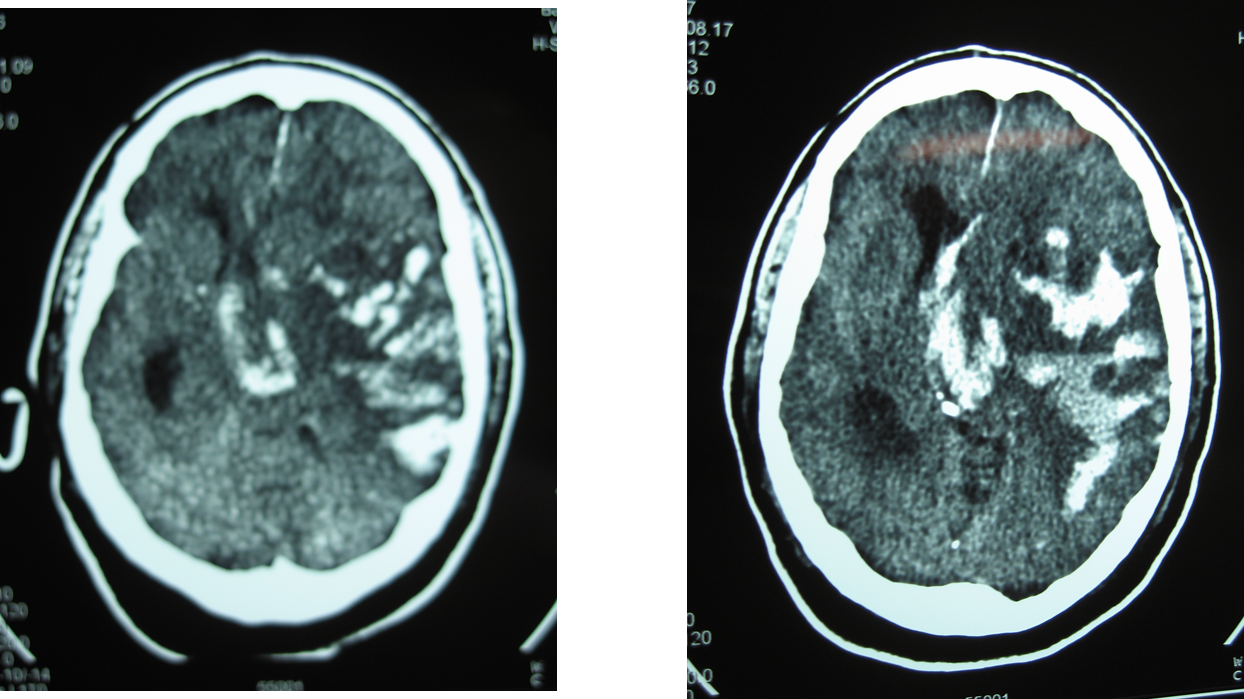

En este caso se trata de una hemorragia en el lugar de la isquemia cerebral en el territorio de la arteria cerebral media izquierda y en el contralateral:

En este caso se cree que además del tratamiento trombolítico, la causa de la hemorragia cerebral puede estar relacionada con una enfermedad subyacente como la angiopatía amiloide (en este caso no se llegó a realizar una RNM cerebral).